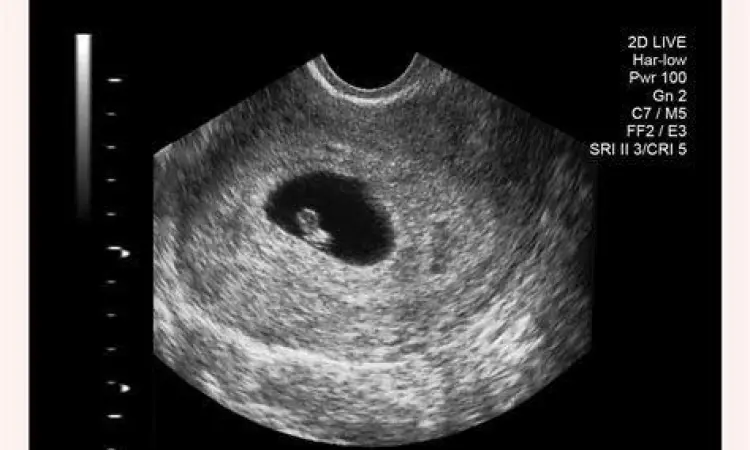

Meskipun ukuran janin masih sangat kecil, jantung janin sebenarnya sudah mulai berdetak secara primitif pada tahap ini, meskipun mungkin belum bisa terdengar jelas melalui alat Doppler biasa. Pemeriksaan melalui USG Transvaginal biasanya sudah bisa memperlihatkan kantung kehamilan (gestational sac) di dalam rahim.

USG pada trimester pertama, terutama antara minggu ke-6 hingga ke-10, dianggap sebagai metode paling akurat (gold standard) untuk menentukan usia kehamilan. Dokter akan mengukur Crown-Rump Length (CRL) atau jarak dari puncak kepala hingga bokong janin. Pada usia 5 minggu, biasanya baru terlihat kantung kehamilan (gestational sac) dengan diameter sekitar 5-10 mm.